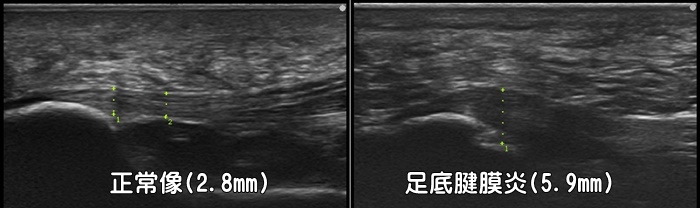

足底腱膜炎

かかとの親指側に着地の際に痛みがあれば足底腱膜炎を疑います。朝の第一歩目の痛み(first step pain)が特徴です。正常な足底腱膜は厚みが4mm未満ですが、足底腱膜炎では4mm以上に肥厚します。また踵骨付着部での腱の肥大が見られます。足底腱膜内にしこりがあれば足底線維腫なども疑います。